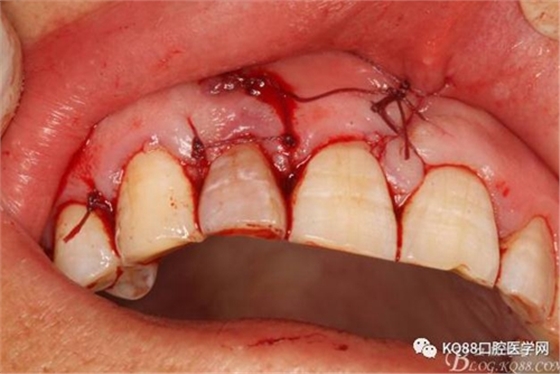

圖6.行唇側(cè)角形切口(11近中垂直切口+齦溝內(nèi)水平切口)垂直切口距離前庭溝約1~2mm。這樣可以減輕術(shù)后腫脹。

圖7. 角形切口中的齦溝內(nèi)切口情況:11號(hào)刀片伸進(jìn)齦溝內(nèi)斜切。

圖8.從垂直切口和水平切口的連接處翻瓣。發(fā)現(xiàn)11和12之間的骨壁有缺損。

圖21.間斷縫合。